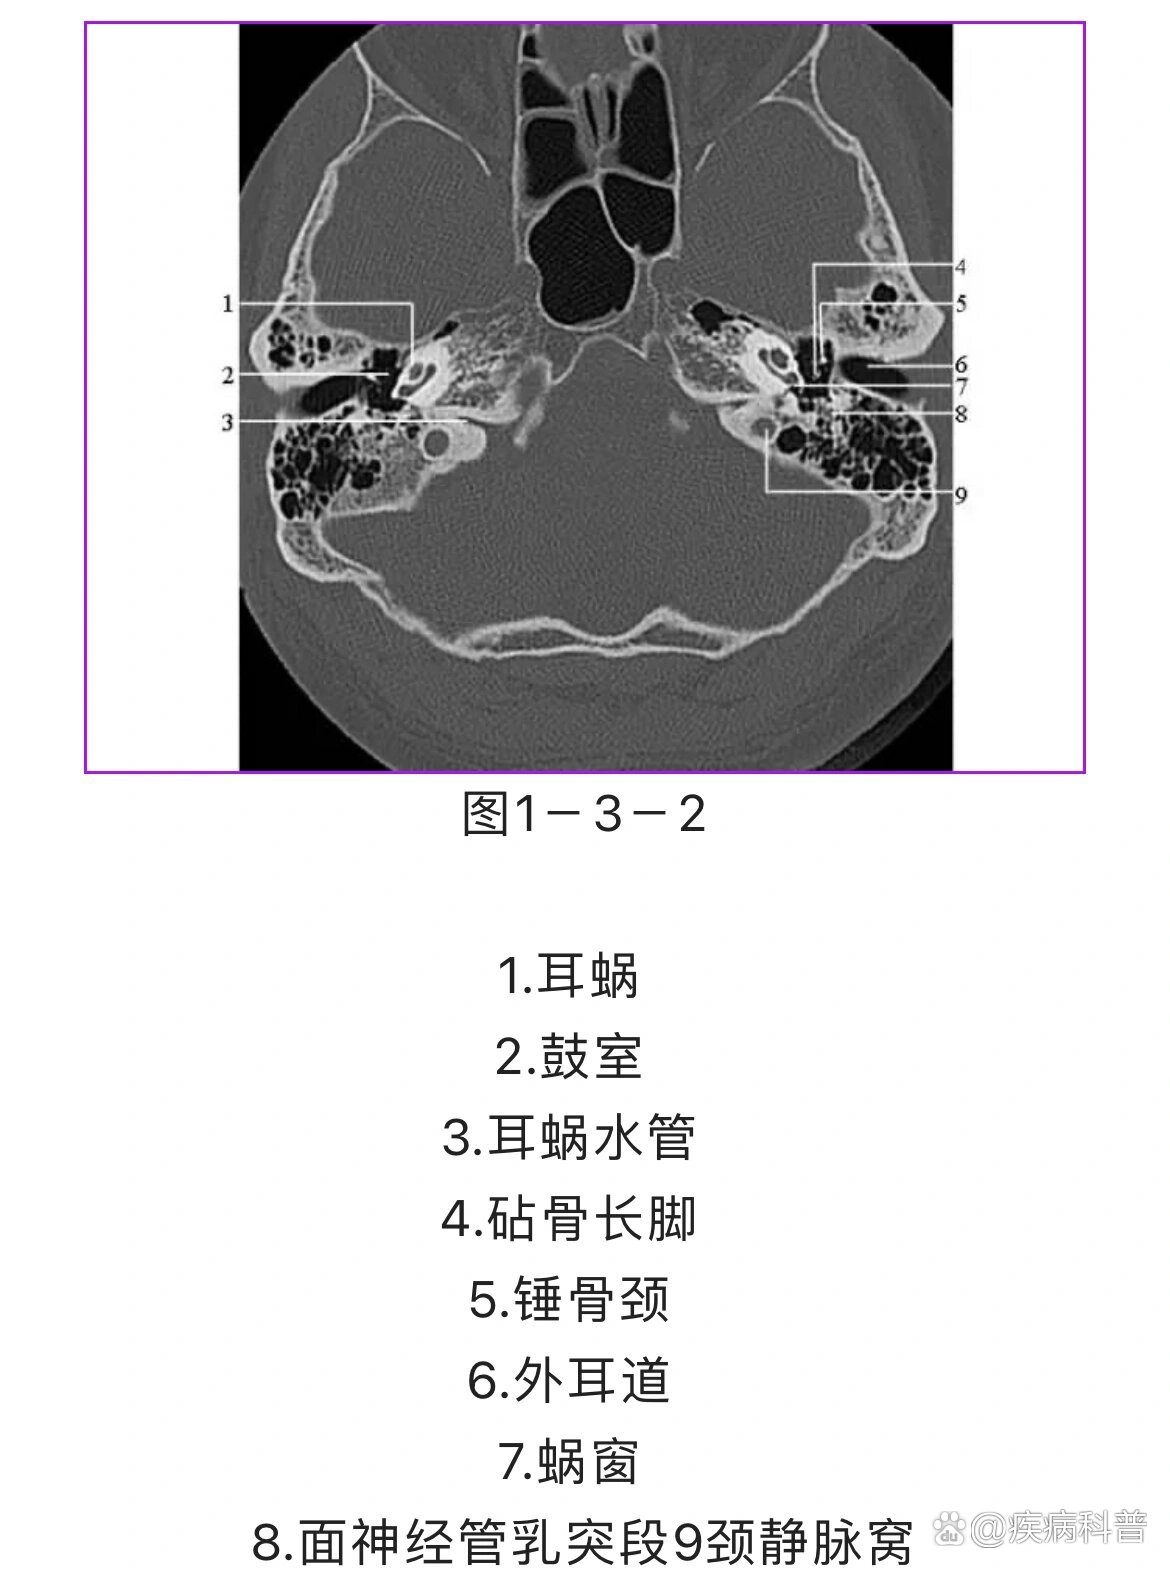

读书笔记:颞骨薄层ct读片心得

原创 颞骨断层轴位ct(完整篇)安阳市中医院耳鼻咽喉科